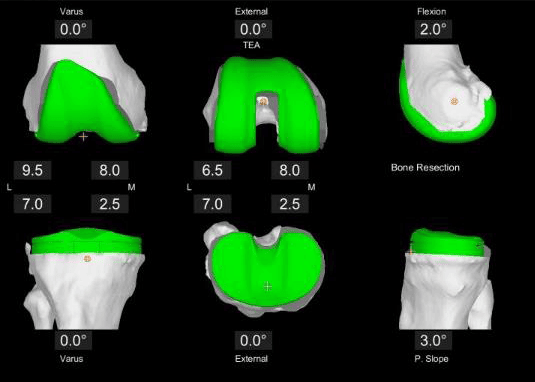

• Durch die CT-basierte 3D-Modellierung der Knochenanatomie können Chirurgen mit dem Mako System einen maßgeschneiderten Operationsplan erstellen und die gewünschte Implantatgröße, -ausrichtung und -passung anhand der individuellen Anatomie der betroffenen Person bestimmen. Das Mako System ermöglicht es Chirurgen auch, den Operationsplan intraoperativ auf virtuelle Weise zu ändern und unterstützt sie bei der Durchführung von Knochenresektionen.

Die OP-Planung – AccuStopTM Technologie

Maßgeschneiderter Operationsplan: vor der Operation wird eine Computertomographie (CT) Ihres Kniegelenks durchgeführt. Auf dieser Grundlage wird dann ein virtuelles 3D-Modell Ihrer individuellen Anatomie entwickelt. Das 3D-Modell ermöglicht es Ihrem Chirurgen, Details zu sehen, die normalerweise nicht mit Röntgenbildern allein zu sehen sind. Die von Mako bereitgestellten Informationen helfen Ihrem Chirurgen bei der Bestimmung der gewünschten Größe und Positionierung Ihres Implantats. Während der gesamten Operation stellt Mako SmartRobotics™ dem Chirurgen Daten in Echtzeit zur Verfügung, damit er die Bewegung und Spannung Ihres neuen Gelenks kontinuierlich beurteilen und Ihren Operationsplan bei Bedarf anpassen kann.

Mit Mako SmartRobotics™ kann Ihr Chirurg einen maßgeschneiderten Operationsplan erstellen und mit Hilfe der AccuStop™ Technologie die für Sie geplanten Schnitte präzise durchführen, was für einige Patient:innen zum Erhalt von Weichteilgewebe und für andere zum Schutz von gesundem Knochen beitragen kann.

• CT-Scan des Gelenks – für detailliertere Informationen über die individuelle Knochenanatomie des Patienten bzw. der Patientin

• Virtuelles 3D-Modell des Gelenks: ermöglicht die genaue Planung für jeden Patienten bzw. jede Patientin

• Individueller präoperativer Plan: für Plananpassungen und funktionale Implantatpositionierung.